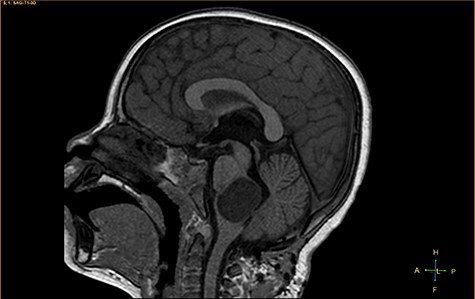

A 3-year-old male, who suffered from a sudden, tonic–clonic seizure, followed by a short period of unconsciousness, was instantly transported to Children’s Hospital 2. The patient’s medical history was normal. No neurological deficits were detected during the clinical assessment, and laboratory tests and electroencephalography were within acceptable ranges. The clinician performed a brain magnetic resonance imaging (MRI) scan, with contrast agent. No lesions were recognized in the supratentorial structures. A clear boundary cystic mass (27 × 25 × 26 mm3) was located in the medulla oblongata, without perilesional vasogenic edema. Hydrocephalus was not observed. The signal intensity of the mass was low on the sagittal T1-weighted image (Fig. 1) and high on the axial T2-weighted image (Fig. 2). On coronal fluid-attenuated inversion recovery imaging, the mass was isointense relative to the parenchyma, but the intensity was higher than that of cerebrospinal fluid (CSF, Fig. 3). On susceptibility-weighted imaging, no indicators of hemorrhage or ossification were observed within the mass. The mass was partially hyperintense on diffusion-weighted imaging (DWI) and slightly hypointense on the apparent diffusion coefficient (ADC) map. The mean ADC values of the parenchyma, mass and CSF were 0.71, 1.3 and 1.59 × 10−3 mm2/s, respectively (Fig. 4). On T1-weighted imaging, with contrast enhancement, the thin wall of the mass was very slightly enhanced, and we observed a tiny nodule inside the mass that was strongly enhanced (Fig. 5). With a provisional diagnosis of pilocytic astrocytoma, the patient underwent surgery to completely eradicate the tumor. Eventually, the histopathological result revealed a typical EC (Fig. 6). The postoperative period was uneventful, and the patient was discharged after 2 weeks.

DWI image and ADC map, showing the CSF, lesion and normal-appearing parenchyma.

Histopathologically, the ECs are filled with protein, keratin and cholesterol. The cyst wall is typically covered with stratified, squamous epithelia, with the outward backing of collagen [3–8]. The appearance on MRI is heavily dependent on the chemical architecture of these intracystic components. The hypointensity observed on T1-weighted images is associated with the crystalline cholesterol pattern, whereas the hyperintensity on T2-weighted images is induced by the keratinaceous element. Occasionally, ECs appear hyperintense on T1-weighted images and hypointense on T2-weighted images, and these are referred to as white ECs [8, 9]. This specific appearance is caused by unusually high proteinaceous concentrations in the cyst. Typically, ECs do not absorb contrast agent vividly. Approximately 35% of ECs are estimated to enhance slightly and peripherally [9]. DWI is the most useful weapon that can be deployed to recognize ECs. When contrasted with the CSF, because of the superior keratinaceous and proteinaceous concentrations and the relatively little aqueous content, ECs generally appear considerably hyperintense on DWI and hypointense on ADC [9, 10].

Although some recommended imaging characteristics exist for ECs, these characteristics are not always persistent or specific [8–10]. Especially in cases of intraparenchymal ECs, provisional diagnosis can be very difficult due to similarities between EC characteristics and those of other brain neoplasms, including glioma [3–10]. In our case, we identified a medulla oblongata mass in a 3-year-old patient, with a lesion ADC of 1.3 × 10−3 mm2/s, and the identification of an enhanced mural nodule in a cystic lesion resulted in the misdiagnosis of pilocytic astrocytoma, a very common, benign, posterior fossa tumor found in children. According to Kannan et al. [10], unlike extra-axial ECs, intraparenchymal ECs do not often exhibit distinctly limited diffusivity.